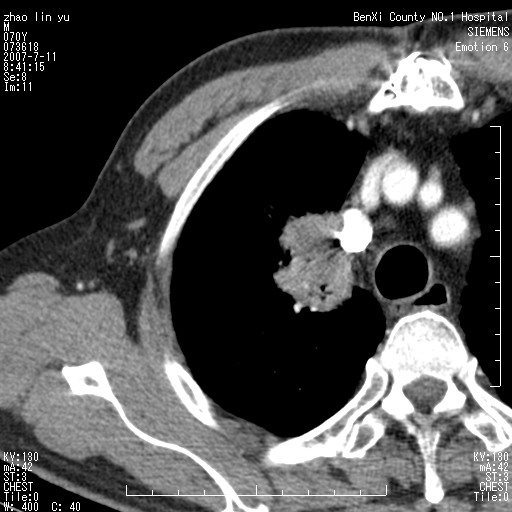

以下是引用王靖旗在2007-7-10 17:12:00的发言:[br] 男、70、咳嗽两个月,半年前换瓣手术,胸片未见异常,于昨天行x片发现右肺上野大片影,行ct扫描,这里是减薄图像,余肺正常。明天晚上会有增强扫描片,到时我会上传。[br][br] 冠状位请大家细看,应该是有意义的,[br][br] 请大家先看平扫发表意见。[br][br]

以下是引用zhangzhongshou在2007-7-10 21:43:00的发言:[br]右肺上叶周围型肺癌,以孤立型细支气管肺泡癌可能性大。